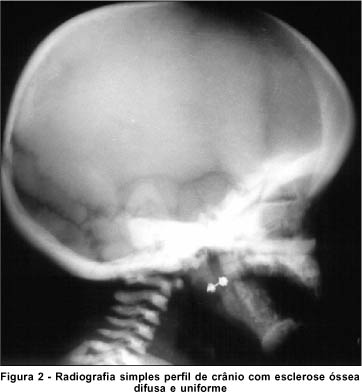

A radiografia de crânio (Figura 2) e membros (Figura 3) demonstra importante esclerose difusa e uniforme, arquitetura totalmente obliterada da calota craniana, ossos da base do crânio, coluna cervical e dos membros inferiores. Tomografia axial computadorizada e ressonância nuclear magnética normais. Leucocitose, trombocitopenia e anemia na avaliação da hematologia pediátrica.

O estudo radiológico demonstra esclerose óssea generalizada. Os focos de esclerose que ocorrem nas vértebras, pélvis e ossos longos distais são os aspectos patognomônicos(1, 2, 6, 8). Nota-se ainda espessamento da base e da calota craniana, perda da díploe e diminuição ou ausência do canal medular(8).